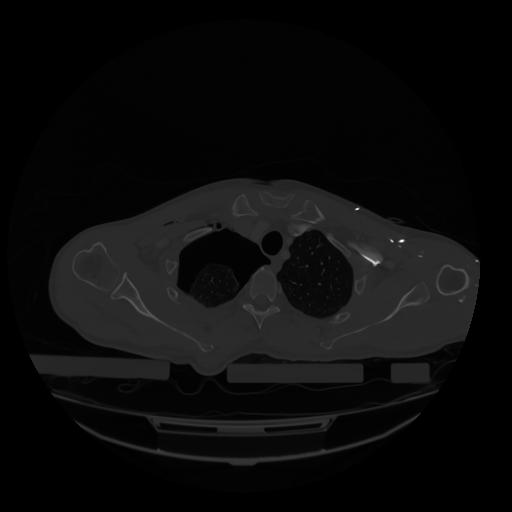

28 CUERPO,CE,Vol,2.0,CUERPO,,